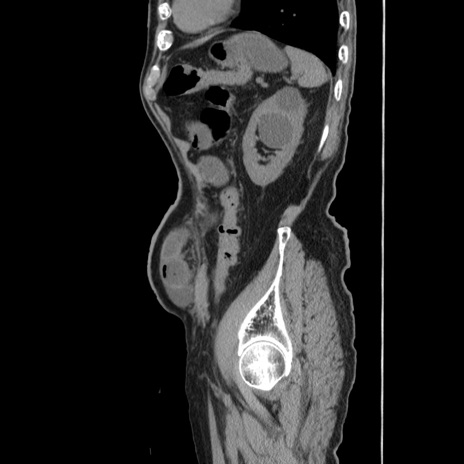

症例24(矢状断像)

【症例】80歳代男性

【主訴】左側腹部痛、嘔吐

【現病歴】本日早朝より左腹部に痛みあり。昼頃嘔吐認めたため、救急要請。

【既往歴】直腸癌(Mile手術)、胆摘

【身体所見】意識清明、BT 35.9℃、BP 221/93mmHg、SpO2 97%(RA) 、腹部:左ストーマ周囲に限局性の腹部膨隆あり。 膨隆部自発痛・圧痛あり・軟。